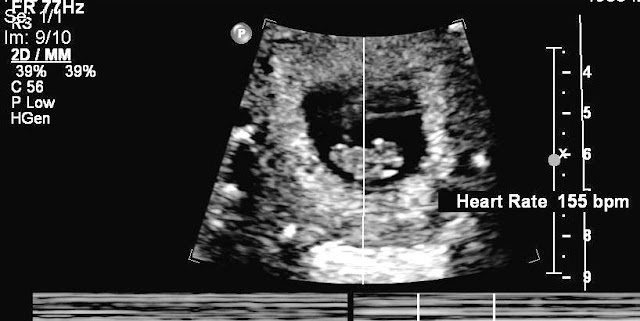

ABOVE: It's always so amazing to be able to 'see' a baby this early on a scan! Even the baby's heart is beating already. I can't even tell what's what yet! But, I saw the heart pumping away!

Quite a buzz.... even though I've seen quite a few baby scans now! They are all special.